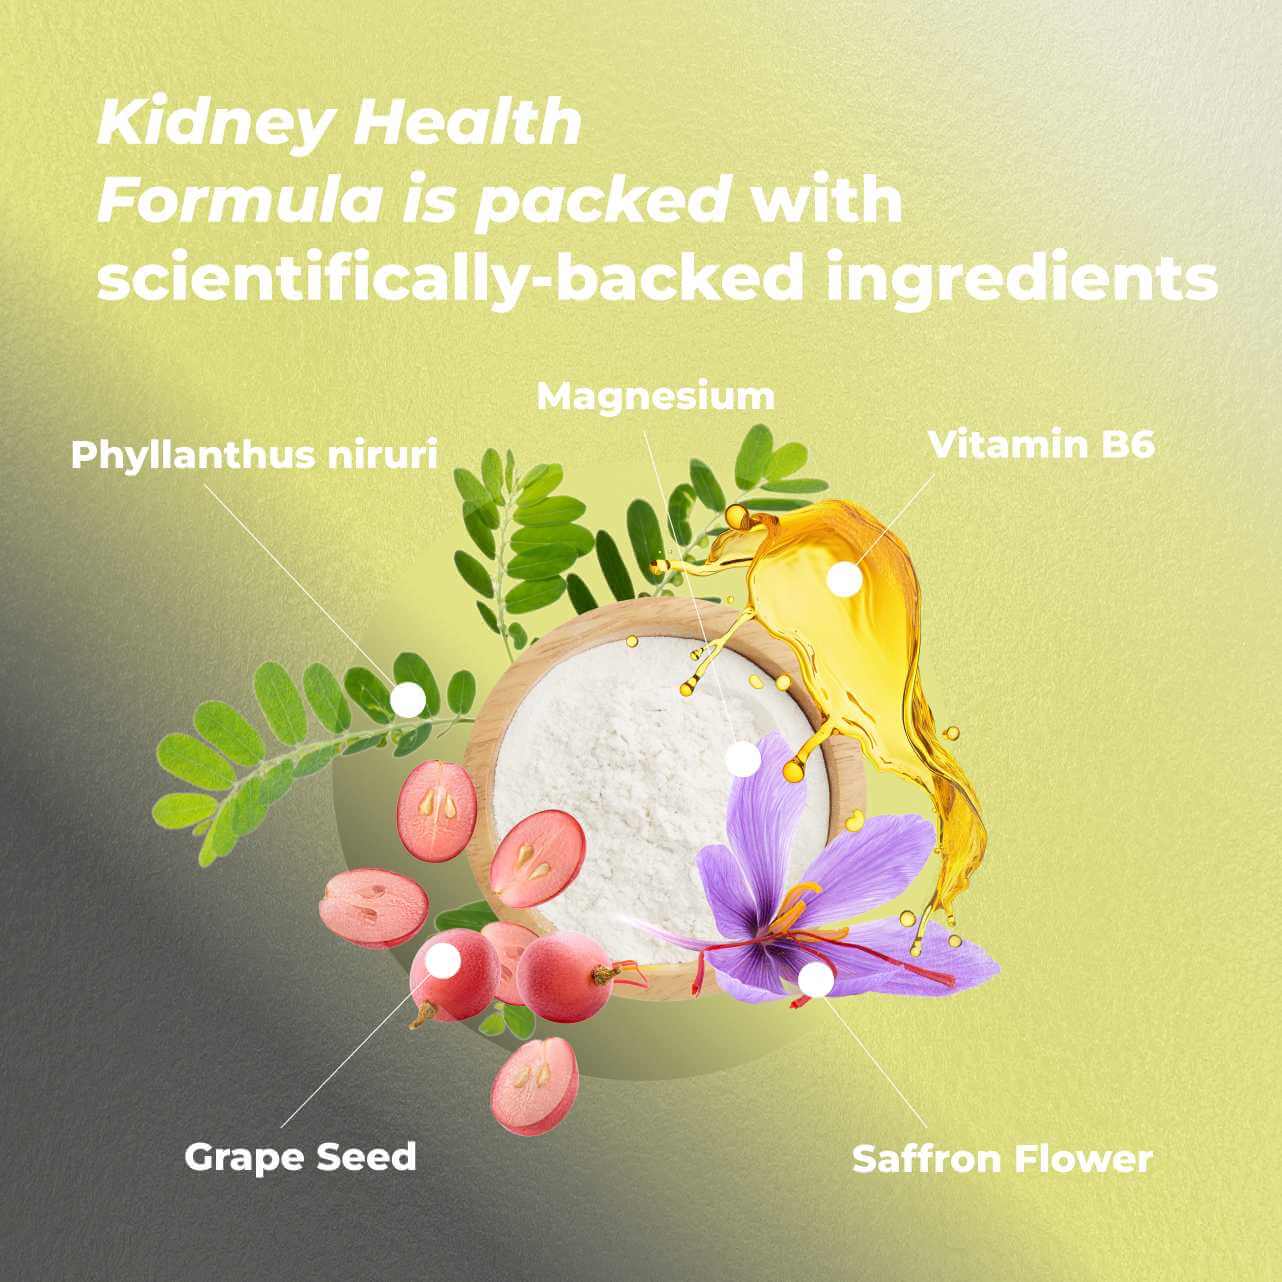

INGREDIENTS:

Vitamin B6

Magnesium

Grape Seed Extract

Phyllanthus niruri

Saffron Flower Extract

Vitamin B6: Clinically proven to have potential for lowering urine oxalate excretion—the most common cause of kidney stones. In a groundbreaking study of 95 patients with elevated oxalate levels, 75% showed significant decrease in urinary oxalate excretion, and 39% returned to normal range after treatment.

Magnesium: A critical mineral for kidney health, associated with improved survival among serious kidney conditions. This specific form—magnesium oxide—could protect against arterial hardening and has shown better kidney outcomes than other magnesium forms.

Grape Seed Extract: A powerful antioxidant complex showing remarkable results in clinical trials. In a 6-month study with 23 chronic kidney patients (stages 2-4), GSE demonstrated significant benefits for kidney function, antioxidant status, and reduced protein levels in urine when combined with standard medication.

Chanca Piedra Extract: Known as the "stonebreaker" for its remarkable ability to inhibit kidney stone formation from oxalate and calcium deposits. In a 12-week study with 56 kidney stone patients, this extract normalized uric acid and oxalate levels, reducing stones in 67.8% of participants.

Saffron Flower Extract: More than just a culinary spice, saffron shows powerful kidney-protective properties. Demonstrated in 25 preclinical studies to guard against kidney-toxic drugs and toxins. A 12-week study with 80 patients showed significant improvements in systolic numbers and renal function.